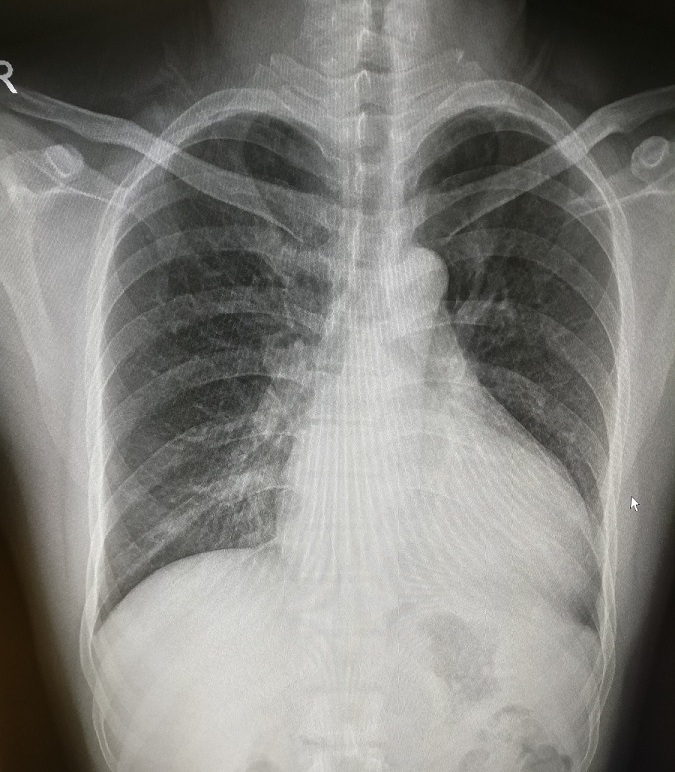

1.左心室增大

常见于高血压病、主动脉瓣病变、二尖瓣关闭不全、先天性心脏病如动脉导管未闭等。见图1。

图1 正位片见左心缘延长,心尖左下移位